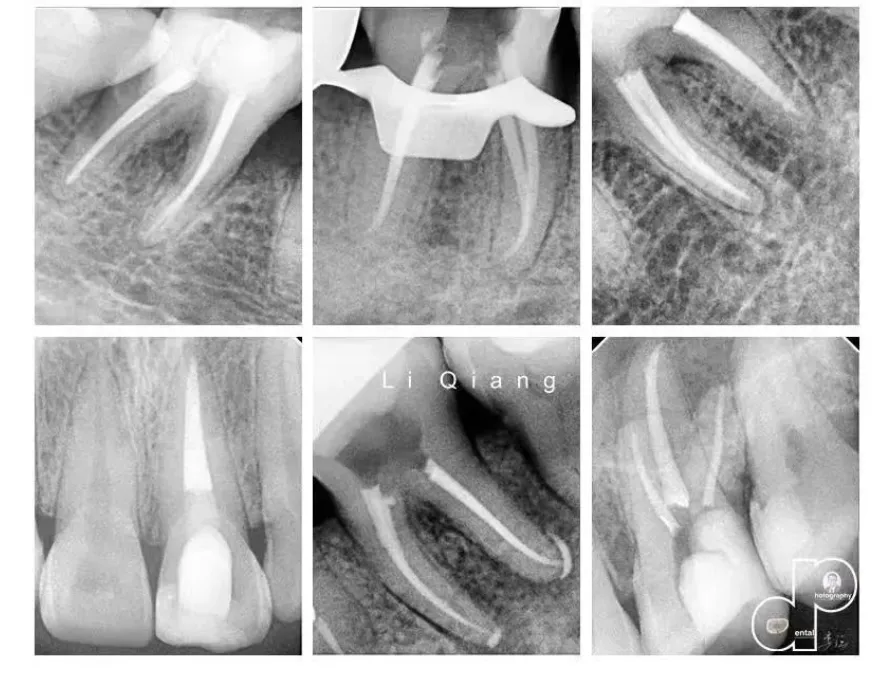

病例展示: